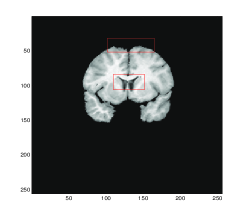

Figure 4 shows the transformed template images for all four methods. We can see that Gaussian curvature gives the best result inside the red boxes in comparison with the diffeomorphic demon, the linear and mean curvature models as depicted in Figure 4 (d).

Figure 4: Test 2: A pair of Brain MR images. Comparison of Gaussian curvature with competing methods. The transformed template image using (a) Model D, (b) Model LC, (c) Model MC, and (d) Gaussian curvature. Notice the differences of these three images inside the red boxes. Considerably more accurate results are obtained, particularly within these significant regions, by employment of the Gaussian curvature model.